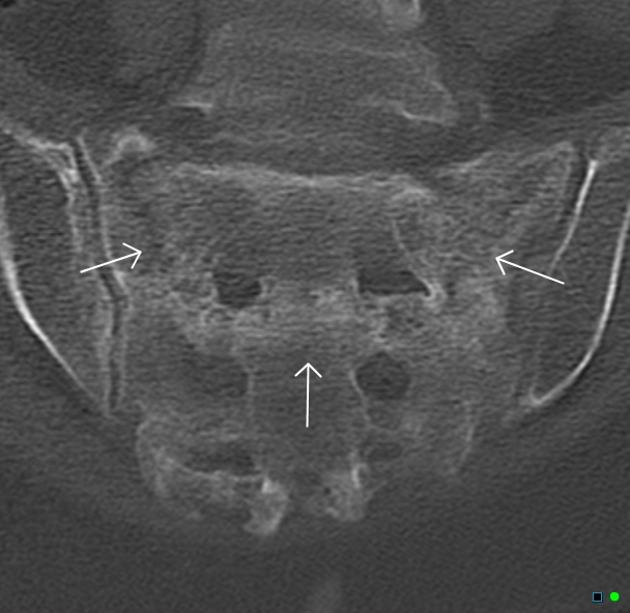

2、单侧或双侧骶骨翼骨皮质断裂,见迂曲纵行骨折线,大致与骶髂关节平行(双侧多见);

3、骶骨体部看见骨折线

4、冠状位上述骨折形成 “H”型 ,故有人称东风本田征(为了方便记忆)

CT影像表现

东风本田征,较为特异性影像表现(冠状位重建)